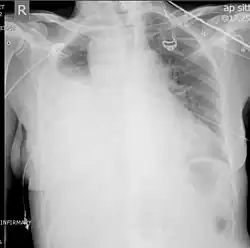

Two chest X-rays: left showing a massive left-sided hemothorax; right showing a massive right hemothorax

A chest X-ray is the most common technique used to diagnosis a hemothorax.[23] X-rays should ideally be taken in an upright position (an erect chest X-ray), but may be performed with the person lying on their back (supine) if an erect chest X-ray is not feasible. On an erect chest X-ray, a hemothorax is suggested by blunting of the costophrenic angle or partial or complete opacification of the affected half of the thorax. On a supine film the blood tends to layer in the pleural space, but can be appreciated as a haziness of one half of the thorax relative to the other.[5] A small hemothorax may be missed on a chest X-ray as several hundred milliliters of blood can be hidden by the diaphragm and abdominal viscera on an erect film. Supine X-rays are even less sensitive and as much as one liter of blood can be missed on a supine film.[24]